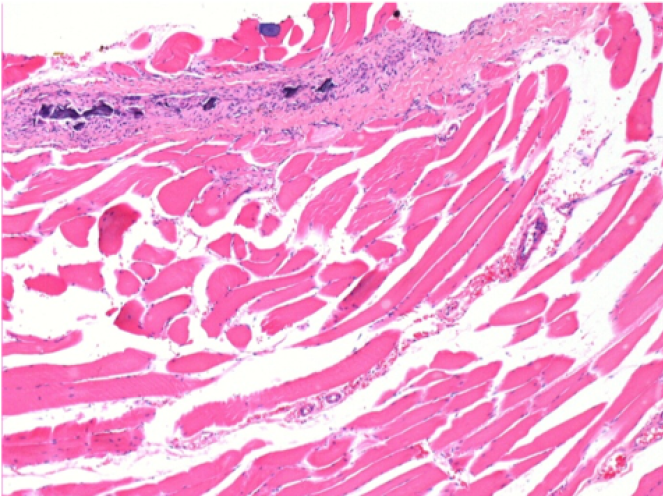

بعد 3 أشهر من حقن إندوبيل

3 أشهر (D90) بعد حقن Endopeel 0.1 مل في العضلة أمام الظنبوب اليمنى.

L : Control-100xD90

R:100xD90